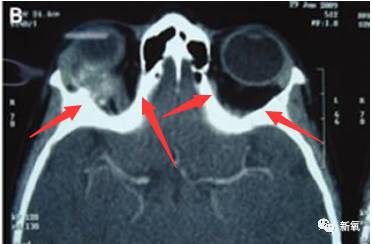

还有一种是单侧的眼球突出,看下面的图,应该能看懂哈,白色部分是骨骼,左侧眼球正常,右侧突出。

看正面就类似下面这样,不过右边的程度会再严重一点。